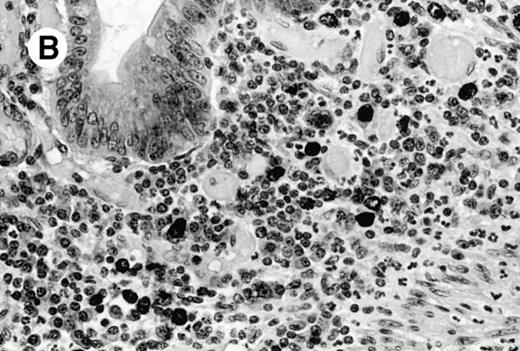

Three cases (cases no. 1 to 3) were located in the nasal cavity. The neoplastic infiltrate consisted of medium and/or large pleomorphic lymphoid cells (Fig 1)intermingled with variable numbers of small lymphoid cells, plasma cells, eosinophils, and histiocytes. Features of angiocentrism and angioinvasion, epitheliotropism, and areas of necrosis were observed in all three cases. Patient no. 4 presented with disease restricted to the lung and an open-lung biopsy was available. The neoplastic infiltrate was composed of large atypical lymphoid cells and was predominantly interstitial without extensive destruction of the normal architecture. Features of angiocentrism, angioinvasion, and epitheliotropism were present (Fig 2A and B). Case no. 5 involved the larynx, extending to the piriform sinus, the ventricle, and the arytenoid. One month later, the lymphoma disseminated to the subcutaneous tissue in the spinal region and biopsy specimens from both sites were available. The neoplastic cells were medium and large, with abundant clear cytoplasm and slightly irregular nuclei with dense chromatin. Epitheliotropism was present in the larynx mucosa. Small foci of necrosis and angiocentrism were seen without angioinvasion. Three patients presented with cutaneous disease. Cases no. 6 and 7 were comparable, as both histories started with necrotic subcutaneous nodules of the thigh, which on histologic analysis were characteristic of cytophagic histiocytic panniculitis without evidence of lymphoma (Fig 3A). Second excisional biopsies of cutaneous nodules obtained 7 and 5 months later, respectively, showed characteristic features of lymphoma in both cases (Fig 3B). However, in case no. 6, skin biopsy specimens showed an epidermotropic PML lymphoma extending to the dermis and the subcutaneous tissue, whereas in case no. 7, the neoplastic infiltrate consisted of a PSC confined to the subcutaneous tissue, admixed with benign histiocytes that showed phagocytosis. Patient no. 8 presented with recurrent skin lesions with spontaneous remission over a period of 10 years. The initial skin biopsies demonstrated an intense epidermotropic neoplastic infiltrate that extended to the superficial and deep dermis composed of atypical PML cells. All cutaneous cases displayed features of angiocentrism, but angioinvasion was observed only in case no. 6 and foci of necrosis in cases no. 6 and 8.

Pulmonary pleomorphic large-cell γδ T-cell lymphoma (case no. 4). (A) Atypical lymphoid cells involve the bronchiolar wall and epithelium; (B) features of angioinvasion; note the preservation of alveolar structures (lung biopsy specimen with hematoxylin-eosin stain); (C) neoplastic cells strongly express TCR γδ. (Immunohistochemical staining on frozen sections with anti-δTCR1 antibody, APAAP technique.)